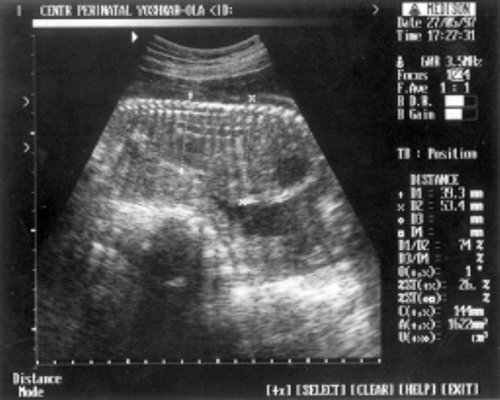

- МРМ (межполушарный размер мозжечка) = 25,6 мм - 23,5-24 нед. (рис. 1)

- ДБ (длина бедра) = 24 мм - 17 нед. (рис. 2)